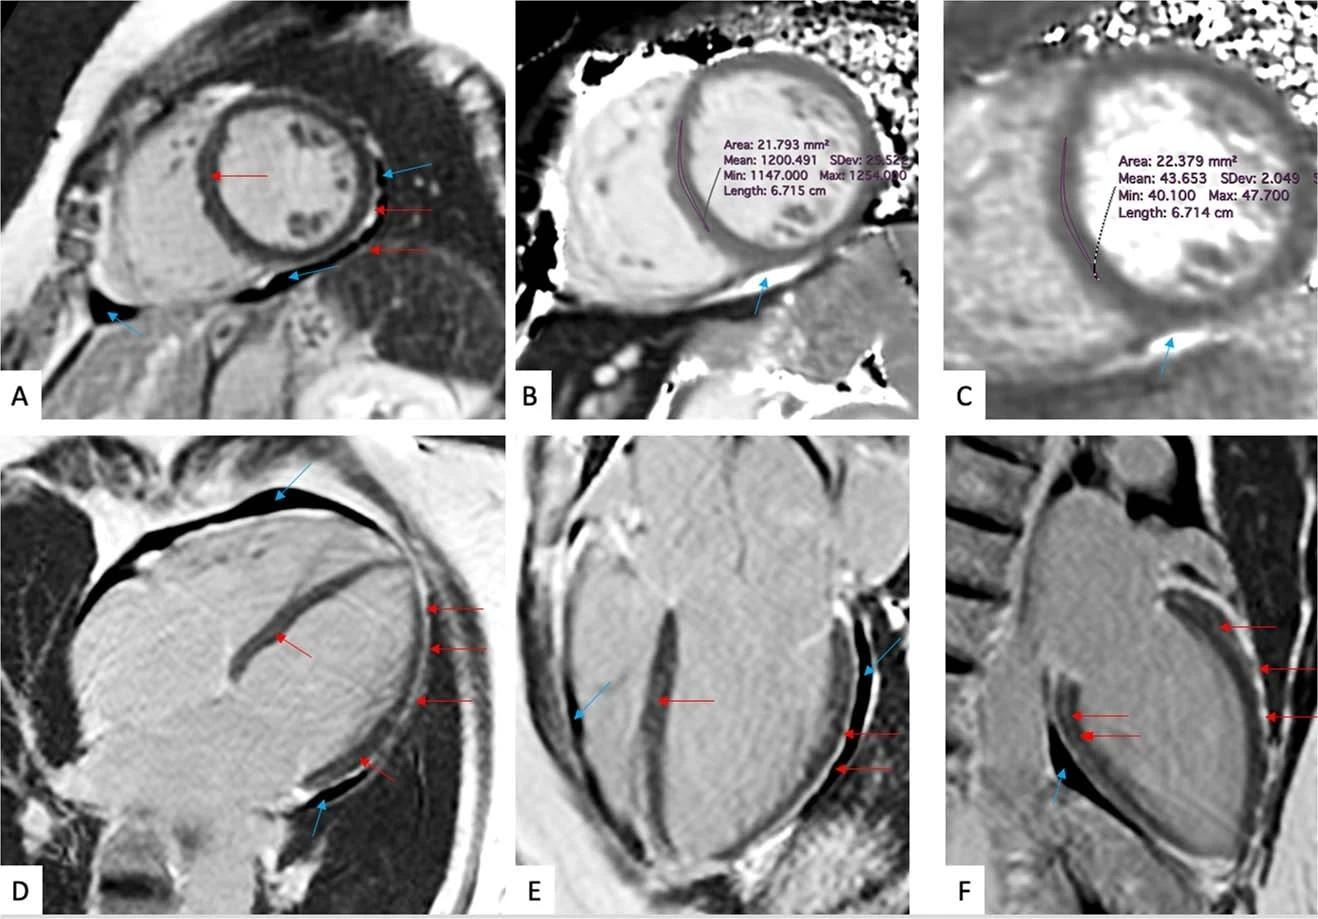

(a-f) Late gadolinium enhancement imaging (A, D-F) and Native T1 (B) and T2 (C) mapping measurements of a 57-year-old woman evaluated 201 days after COVID-19 infection. This individual reported dyspnea, palpitations, and chest pain, worsening on minimal exertion. Late gadolinium enhancement imaging allows to visualize regional accumulation of the gadolinium-based contrast agent along the outer rim of the myocardial free wall (red arrows), as well as within the thickened pericardial layers, separated by small amounts of pericardial effusion (blue arrows).

CMR imaging techniques can detect diffused inflammatory myocardial involvement (a non-specific measure of abnormal myocardium) by T1 mapping and myocardial water content by T2 mapping. The late gadolinium enhancement (LGE) denoted regional myocardial injury. On the other hand, the accumulation of gadolinium contrast agents helped visualize thickened pericardial layers.

Participants with cardiac symptoms also had markedly higher myocardial native T1 mapping values. However, they had similar blood biomarkers, including C-reactive protein (CRP) and N-terminal pro-brain natriuretic peptide (NT-proBNP). Furthermore, the authors noted that 64% of participants had detectable troponin. Only a few participants had structural heart diseases. Overall, CMR imaging indicated inflammatory cardiac involvement after COVID-19 as a pathophysiological commonality, irrespective of the expression of cardiac symptoms. However, since overall troponin levels were low and unrelated to the presence of cardiac symptoms, it suggested that cardiac symptoms manifested as increased myocardial wall stress and not necrosis.